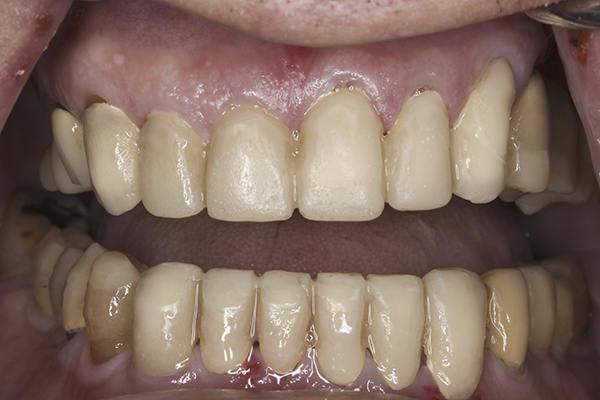

(24.) Provisionals, anterior, closed view.

Figure 24

(36.) Postoperative anterior, closed view. Note the position of the upper and lower canines to provide canine guidance.

Figure 36